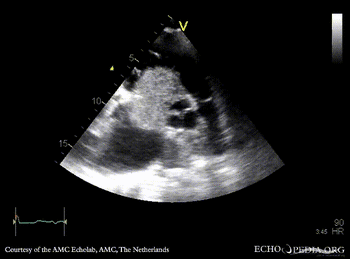

Case 152